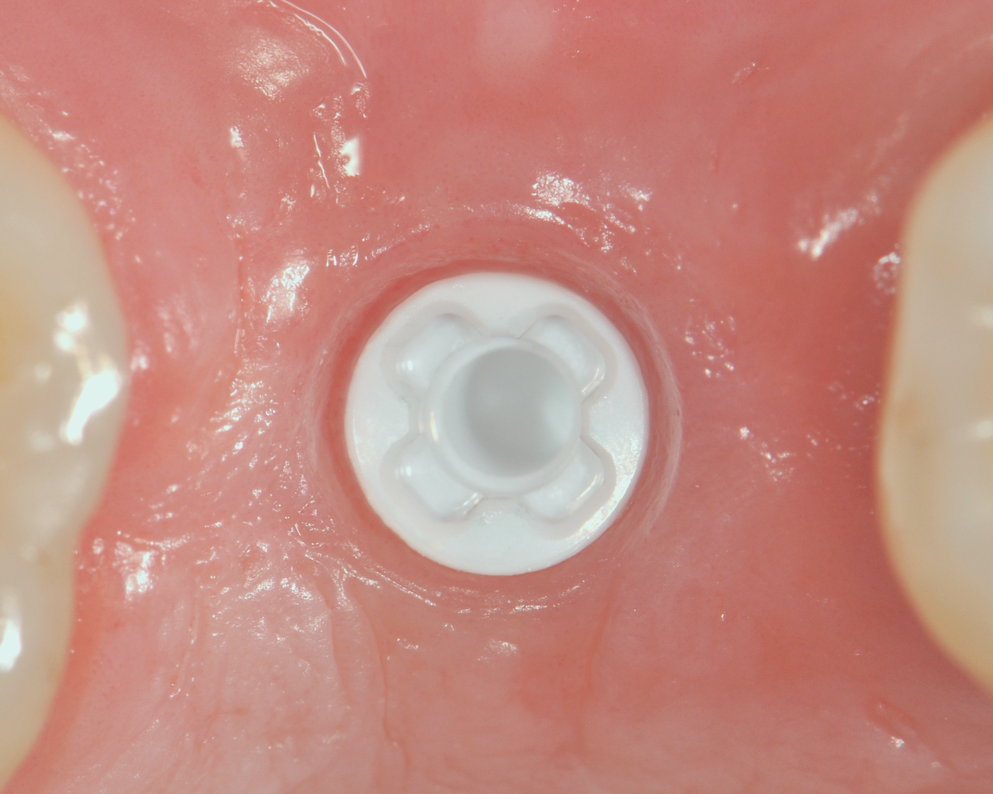

Fig 7. Restoration and screw-retained abutment with metal-free screw (60% carbon fiber in a polyetheretherketone [PEEK] matrix).

Figure 7

Fig 11. Screw-retained removable abutment in situ.

Figure 11